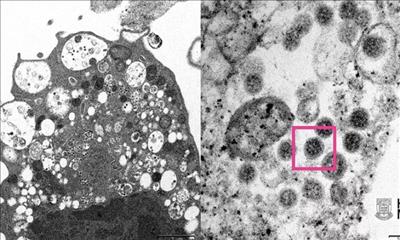

Một nhóm nhà khoa học quốc tế nhận dạng kháng thể có khả năng vô hiệu hóa omicron và những biến chủng nCoV khác. Những kháng thể này nhắm vào khu vực trên gai protein của virus không thay đổi khi virus đột biến.